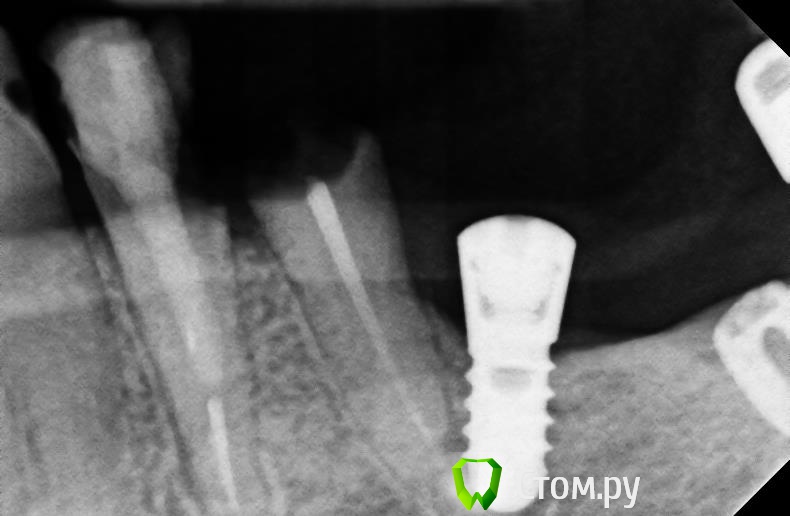

bullbull Опубликовано 20 ноября, 2013 Поделиться Опубликовано 20 ноября, 2013 Вот это имплантат по касательной! На первых двух фото 2011 год (винт установлен 2008-2009). На последнем фото пара недель назад перед удалением зуба. В лунке пальпируется верхушка винта. Удалять железо не хочет, так как ничего не беспокоит. Ссылка на комментарий